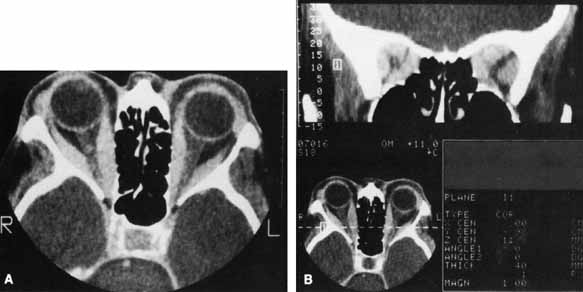

The increased orbital volume is usually due to both extraocular muscle and orbital fat expansion; however, patients younger than 40 years of age are more likely to exhibit orbital fat enlargement in the absence of muscle enlargement, whereas patients over 70 years are more prone to severe, fusiform muscle enlargement without significant changes in orbital adipose tissue volume.49 Forbes et al.11 reported enlargement of the fat compartment in 46% of patients with TO, whereas 8% had increased fat compartments with normal muscle volumes (Fig. 4).

Fig. 4 Axial CT scan of patient with thyroid orbitopathy, extreme proptosis, and no clinical evidence of optic neuropathy. Note the increase in orbital fat volume without significant extraocular muscle enlargement. In this case axial proptosis has allowed spontaneous decompression of increased orbital volume.

CT is not necessary in most patients who present with a clinical picture and supporting laboratory evidence of Graves' disease. It is, however, indicated when optic neuropathy is suspected, before orbital decompression, to examine the anatomic relationship of the orbit to both the sinus cavities and the cribriform plate, in patients with atypical proptosis or motility disturbances; or instead of ultrasonography to detect early thyroid orbitopathy in patients with equivocal results of laboratory tests. Like ultrasonography, CT allows reliable identification of even minimal enlargement of the recti muscles.40 Of those patients with clinical unilateral thyroid orbitopathy, CT will detect subclinical enlargement of the extraocular muscles on the contralateral side in 50%.75

The most characteristic CT finding in thyroid orbitopathy is enlargement of the extraocular muscles, which is usually bilateral and symmetric and has a fusiform configuration, with sharply defined borders and sparing of the tendinous insertions. Atypical cases with tendon involvement and blurred muscle margins have been described.75

The pattern of muscle enlargement on CT parallels that seen clinically. The inferior rectus is the most commonly involved, followed by the medial rectus, superior rectus, and lateral rectus. Other findings include proptosis and anterior prolapse of the orbital septum due to excessive orbital fat and muscle swelling (see Fig. 4).76 Also, lacrimal gland enlargement and bone remodeling without erosion can occur.75 Patients at risk for developing optic neuropathy may also have severe apical crowding, a dilated superior ophthalmic vein, and anterior displacement of the lacrimal gland.68 Of these, apical crowding is the most sensitive indicator for the presence of optic neuropathy (Fig. 5A).56 Both axial and coronal CT cuts should be obtained; the coronal plane is needed to assess the enlargement of the extraocular muscles at the apex (see Fig. 5B).